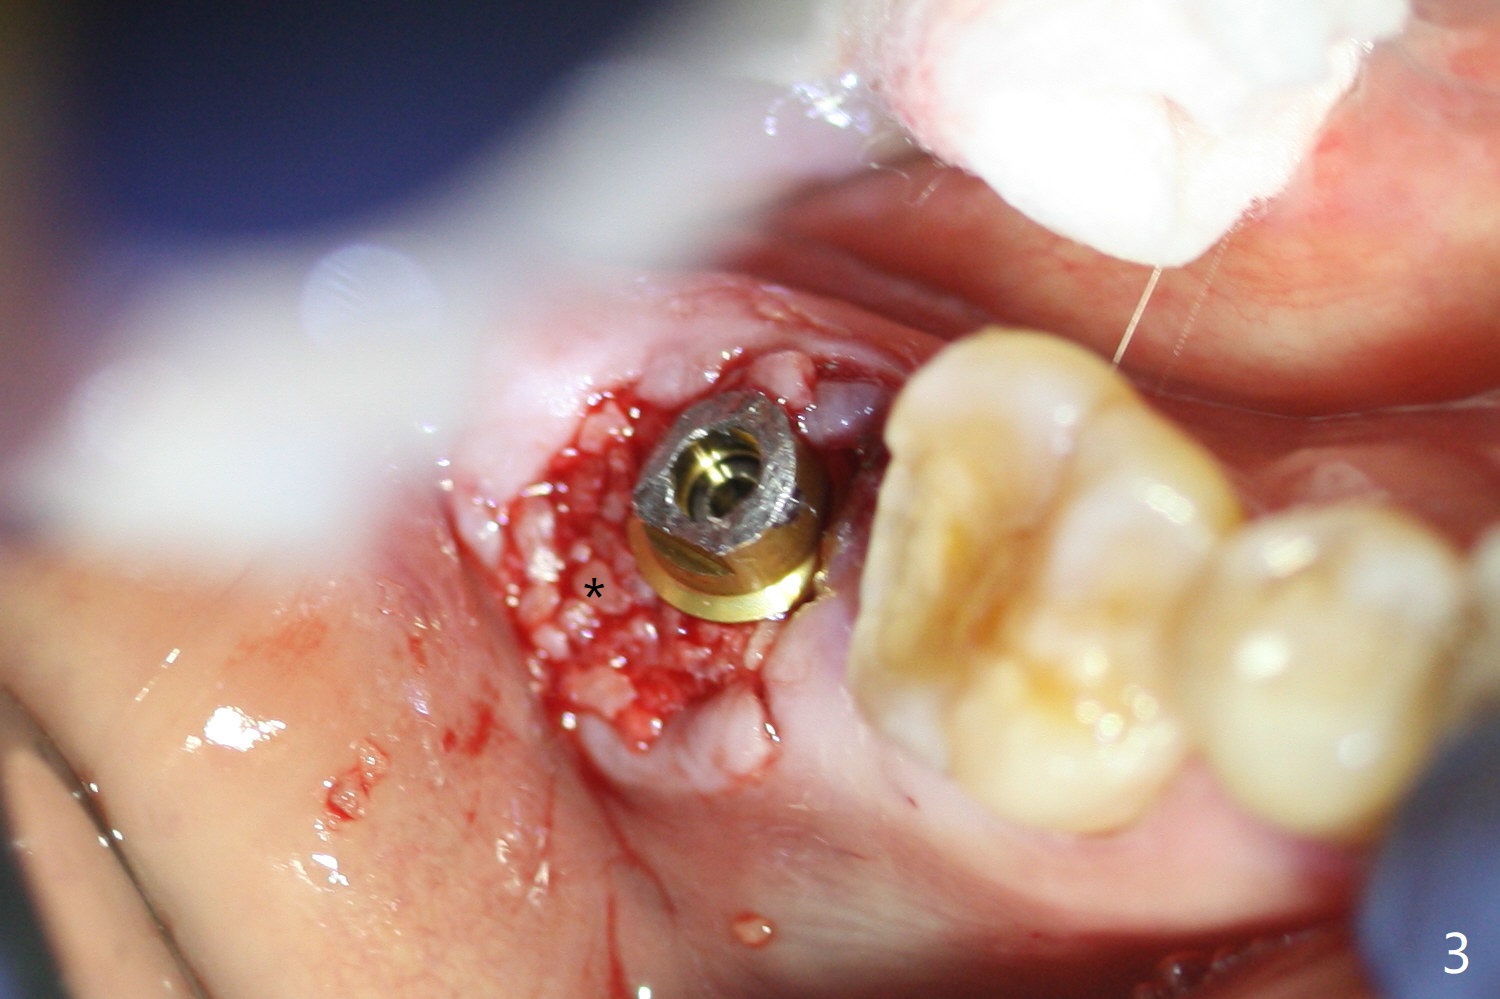

The residual roots of the tooth #31 are lower buccal (Fig.1 B), which in fact is molded and worn by the supraerupted tooth #2. When the tooth is extracted (Fig.2) and an implant, abutment (Fig.3 gold colored) and allograft (*) are placed, the abutment has to be trimmed. An atypical immediate provisional is fabricated by spreading setting acrylic over the abutment and bone graft (Fig.4 P) with occlusal equilibrium. Advantages of the guided surgery are good position (Fig.3 buccolingual), trajectory and depth (Fig.5,6) of the implant. The buccodistally exposed implant threads are packed with allograft in sufficient amount (Fig.3,5,6 *). The atypical immediate provisional breaks down and dislodges 3 weeks postop (Fig.7). In fact the implant plateau is exposed buccally. A monojet is given to the patient for self cleansing. He is instructed to return in 3 weeks. The exposed implant threads are covered 1.5 months postop (Fig.8). Incomplete abutment seating (Fig.9 <) was not noted until 1 year 3 month post cementation when the crown was mobile (Fig.10). A 6x3 mm healing abutment is placed. Three days later, the crown is sectioned and separated from the abutment. The latter returns to place; due to angulation associated with PA, the gap between the implant and abutment is indistinct (Fig.11). Bitewing is taken; the gap exists (Fig.12 <). The abutment seems to be seated deep; there is apparently soft tissue interference. A 5.2x4(2) mm abutment remains incompletely seated (Fig.13 >). A 5.2x4(3) mm one is completely seated (Fig.14 <). Zirconium crown with an access hole is cemented in the mouth. The crown and abutment is then removed for residual cement removal and reseated and torqued (Fig.15). Four months later, the Zirconium crown is fractured (Fig.16). Impression is retaken for high noble metal crown without access hole for strength (Fig.17).